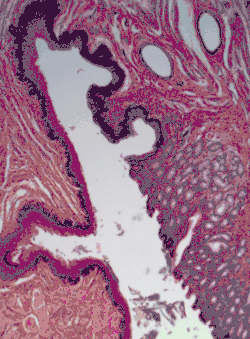

H&E stain of biopsy of normal esophagus showing the stratified squamous cell epithelium.

A stratified squamous epithelium consists of squamous (flattened) epithelial cells arranged in layers upon a basal membrane. Only one layer is in contact with the basement membrane; the other layers adhere to one another to maintain structural integrity. Although this epithelium is referred to as squamous, many cells within the layers may not be flattened; this is due to the convention of naming epithelia according to the cell type at the surface. In the deeper layers, the cells may be columnar or cuboidal.[1] There are no intercellular spaces. This type of epithelium is well suited to areas in the body subject to constant abrasion, as the thickest layers can be sequentially sloughed off and replaced before the basement membrane is exposed. It forms the outermost layer of the skin and the inner lining of the mouth, esophagus and vagina.[2]